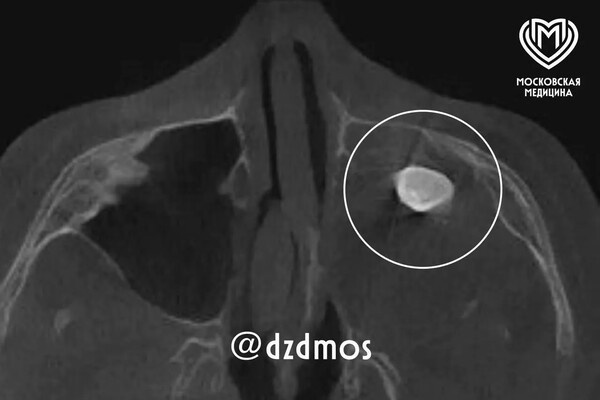

Московские врачи удалили подростку зуб, выросший в носу

Врачи Филатовской больницы в Москве удалили подростку зуб, который вырос в носу. Об этом сообщает столичный депздрав в своем канале в Max. Уточняется, что 15-летний мальчик попал в больницу с жалобами на асимметрию лица и заложенность носа. До этого, как отметили в депздраве, мальчика осматривали врачи частной клиники — они нашли в гайморовой пазухе сформировавшийся зуб и предложили удалить его. Родители подростка решили выслушать второе мнение и обратились за консультацией в Филатовскую больницу, где по результатам консилиума врачи предложили провести операцию по Колдуэллу-Люку, то есть обеспечить доступ через верхнюю десну, чтобы вернуть ему возможность нормально дышать. Сделав разрез, врачи обнаружили новообразование, внутри которого и находился зуб, рассказал хирург-оториноларинголог Вугар Достиев. По его словам, доброкачественная опухоль оказалась тератомой — эмбрионально-клеточным новообразованием, внутри которого могут находиться элементы тканей, несвойственные этому участку тел

Сделав разрез, врачи обнаружили новообразование, внутри которого и находился зуб, рассказал хирург-оториноларинголог Вугар Достиев. По его словам, доброкачественная опухоль оказалась тератомой — эмбрионально-клеточным новообразованием, внутри которого могут находиться элементы тканей, несвойственные этому участку тела.